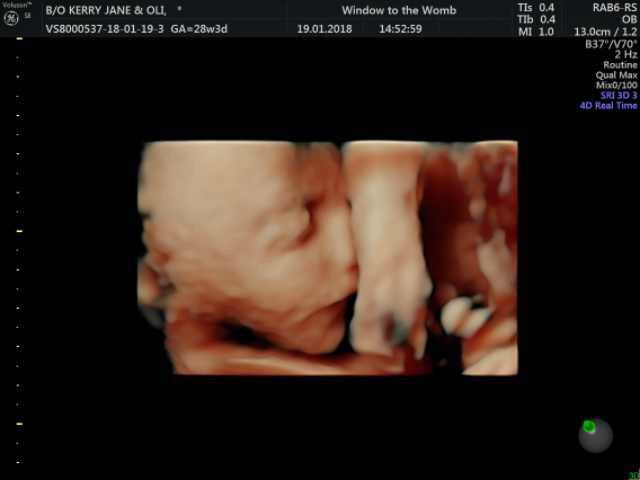

Our Bexleyheath clinic had the pleasure of welcoming actor Oli Regan and his partner into their clinic for a 4D HDlive scan.

Opting for a 4D + Well-being (Born to Be a Star) package with HDlive, Oli and partner began with a well-being check of baby in 2D, where our sonographers took a peek at little one and check all is well. All our scans include a diagnostic report to take away. Then they were introduced to little one in 4D! Our 4D + Well-being Package (Born to Be a Star) includes a scan movie recording, photo prints and lots more! Bexleyheath is one of a selection of our clinics who do HDlive scanning – the latest technology which gives you an even clearer image of baby.

Oli & partner were introduced to baby in HDlive!